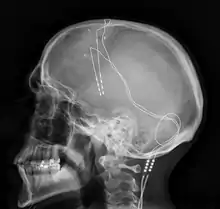

Deep brain stimulation (DBS) is a neurosurgical procedure involving the placement of a medical device called a neurostimulator (sometimes referred to as a "brain pacemaker"), which sends electrical impulses, through implanted electrodes, to specific targets in the brain (brain nuclei) for the treatment of movement disorders, including Parkinson's disease, essential tremor, and dystonia.[1] While its underlying principles and mechanisms are not fully understood, DBS directly changes brain activity in a controlled manner.[2][3]

Components and placement

The DBS system consists of three components: the implanted pulse generator (IPG), the lead, and an extension. The IPG is a battery-powered neurostimulator encased in a titanium housing, which sends electrical pulses to the brain that interfere with neural activity at the target site. The lead is a coiled wire insulated in polyurethane with four platinum-iridium electrodes and is placed in one or two different nuclei of the brain. The lead is connected to the IPG by an extension, an insulated wire that runs below the skin, from the head, down the side of the neck, behind the ear, to the IPG, which is placed subcutaneously below the clavicle, or in some cases, the abdomen.[9] The IPG can be calibrated by a neurologist, nurse, or trained technician to optimize symptom suppression and control side effects.[30]

DBS leads are placed in the brain according to the type of symptoms to be addressed. For non-Parkinsonian essential tremor, the lead is placed in either the ventrointermediate nucleus of the thalamus or the zona incerta;[31] for dystonia and symptoms associated with PD (rigidity, bradykinesia/akinesia, and tremor), the lead may be placed in either the globus pallidus internus or the subthalamic nucleus; for OCD and depression to the nucleus accumbens; for incessant pain to the posterior thalamic region or periaqueductal gray; and for epilepsy treatment to the anterior thalamic nucleus.[32]

All three components are surgically implanted inside the body. Lead implantation may take place under local anesthesia or under general anesthesia ("asleep DBS") such as for dystonia. A hole about 14 mm in diameter is drilled in the skull and the probe electrode is inserted stereotactically, using either frame-based or frameless stereotaxis.[33] During the awake procedure with local anesthesia, feedback from the person is used to determine the optimal placement of the permanent electrode. During the asleep procedure, intraoperative MRI guidance is used for direct visualization of brain tissue and device.[34] The installation of the IPG and extension leads occurs under general anesthesia.[35] The right side of the brain is stimulated to address symptoms on the left side of the body and vice versa.